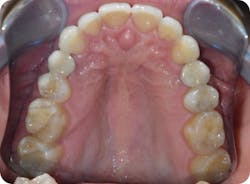

- His narrow maxilla had a corresponding vaulted palate, which is clearly visible (figure 3).

- He had improper buccolingual inclination as most of the posterior teeth had excess lingual inclination (figure 4).